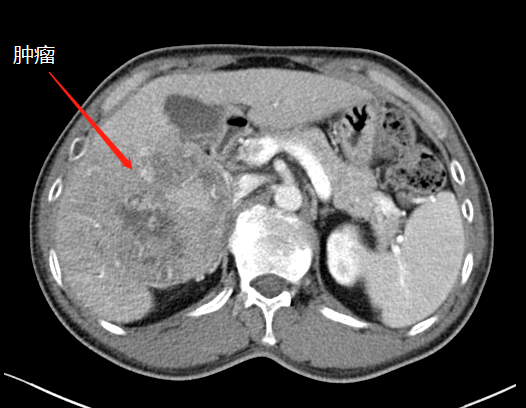

二次手術(shù)完整切除腫瘤

于是,專家團(tuán)隊(duì)便于10月中旬為患者實(shí)施了第二階段腫瘤切除術(shù),在此過程中,由于患者同時合并腹繭癥,通過第一次手術(shù)的刺激腹腔內(nèi)粘連非常嚴(yán)重,手術(shù)遭遇了巨大的困難,最后經(jīng)過近7小時左右的艱苦奮戰(zhàn),攻堅(jiān)克難,終于完整切除了患者右肝的巨大腫瘤,手術(shù)取得了成功,患者重獲新生。

術(shù)后,患者經(jīng)過10多天的恢復(fù)治療,順利康復(fù)出院。出院后,經(jīng)科室多次電話回訪,現(xiàn)患者身體狀況和生活質(zhì)量良好。